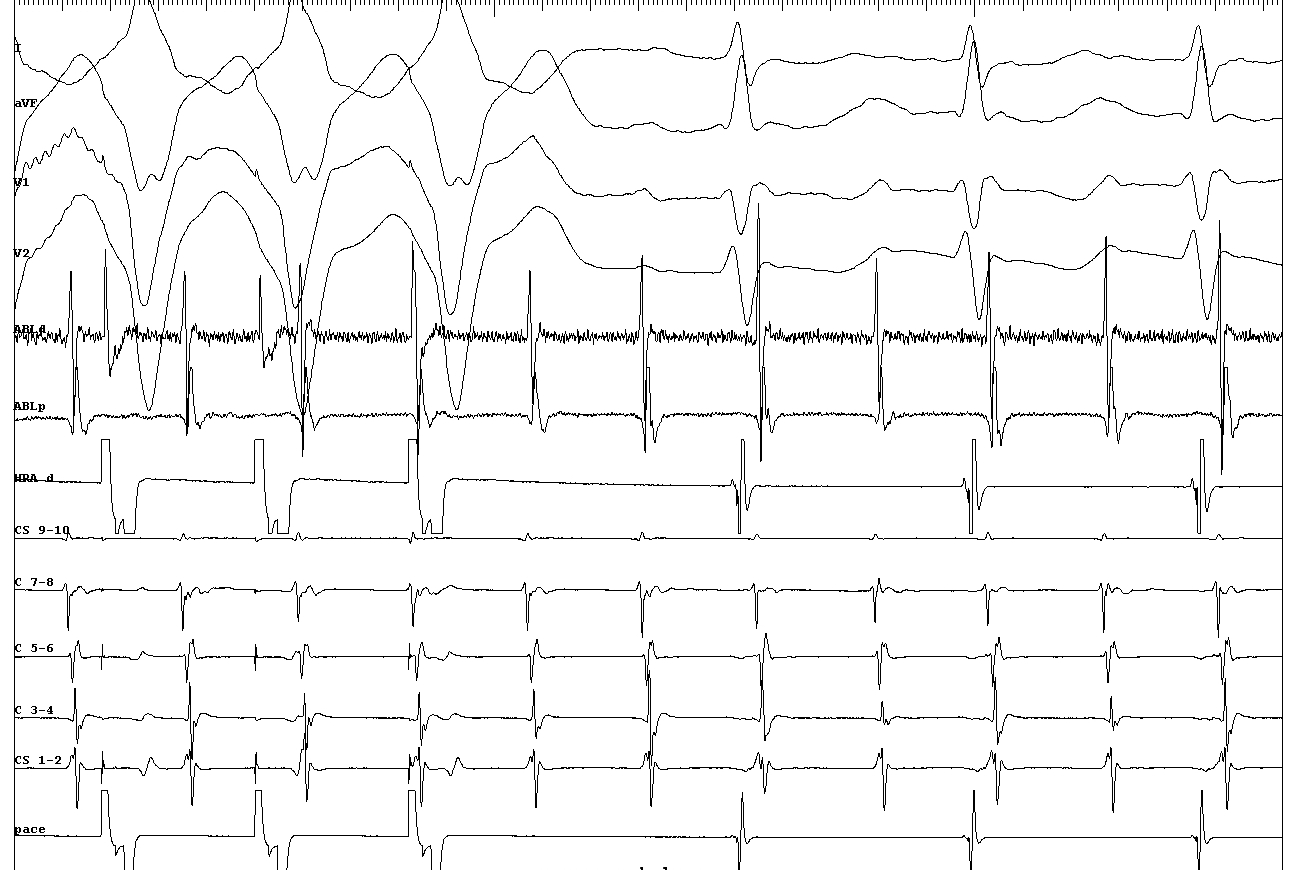

cs_activation.png

Approach to catheter ablation of left atrial �utters Steven M. Markowitz MD, George Thomas MD, Christopher F. Liu MD, Jim W. Cheung MD, James E. Ip MD, Bruce B. Lerman MD. JCE 2019

entrainment_three_sites.png

Miyazaki H, Stevenson WG, Stephenson K, Soejima K, Epstein LM. Entrainment mapping for rapid distinction of left and right atrial tachycardias. Heart Rhythm. 2006 May;3(5):516-23. doi: 10.1016/j.hrthm.2006.01.014. Epub 2006 Feb 28. PMID: 16648054.